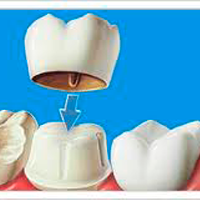

√ Prótese Fixa: São próteses que podem substituir um ou mais dentes perdidos e podem precisar de apoio nos dentes vizinhos. Não podem ser removidas pelo paciente.Também conhecida como ponte fixa, coroa, jaqueta, pivô.